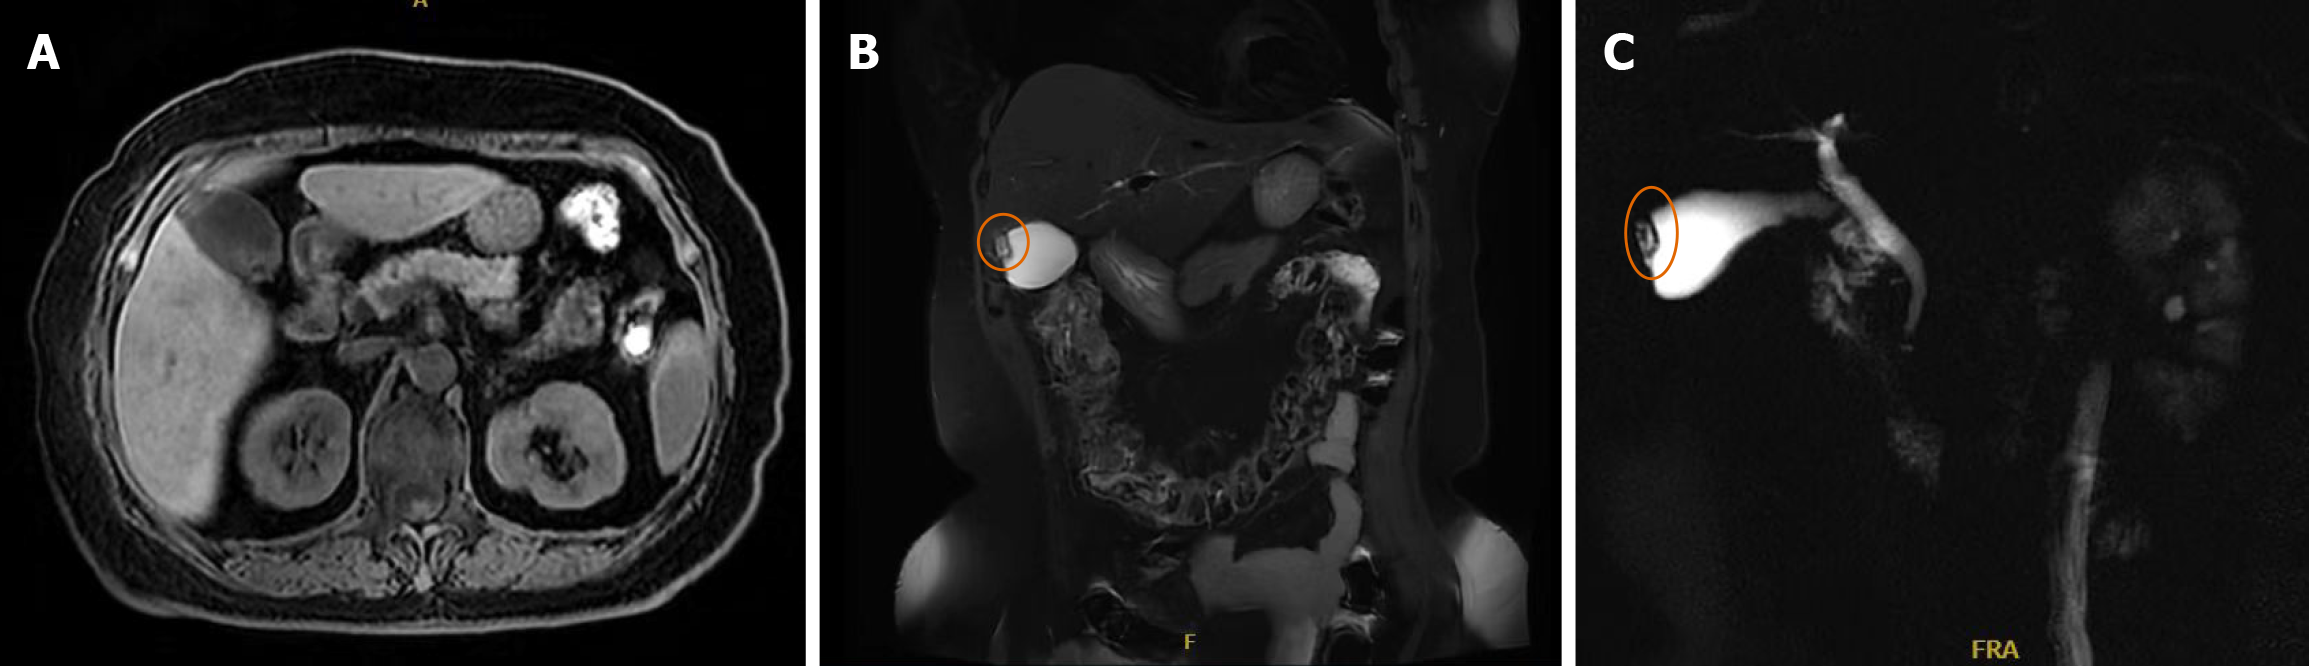

Figure 1 Magnetic resonance cholangiopancreatography.

A-C: A patchy lesion at the gallbladder fundus demonstrated iso-intensity on T1-weighted images and slightly increased signal on T2-weighted images, with small cystic T2 hyperintense foci within, suggesting the possibility of gallbladder adenomyomatosis. The liver, spleen, and pancreas showed no obvious morphological or size abnormalities. No significant abdominal lymphadenopathy or ascites was detected.